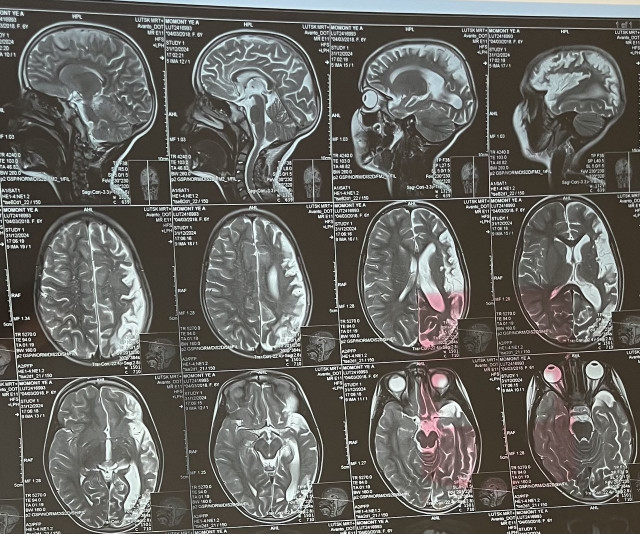

«При першому клінічному епізоді ми ставили діагноз аутоімунний енцефаліт, адже бачили характерні зміни на МРТ, а також зміни в об’єктивному стані Лізи. Через рік відзначилась негативна динаміка на МРТ головного мозку, зміни на електроенцефалографії (ЕЕГ), які характерні для енцефаліту Расмуссена. Саме тому лише через рік ми визначили точний діагноз Лізи. Специфічного лікування енцефаліту Расмуссена, на жаль, не існує, адже достеменно невідома точна причина виникнення цієї хвороби.